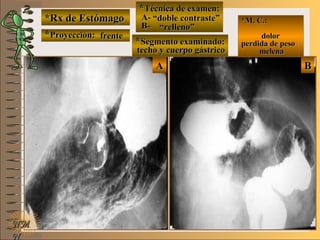

*Rx de Estómago*Rx de Estómago

**Proyección:Proyección:

**Técnica de examen:Técnica de examen:

**Segmento examinado:Segmento examinado:

*M. C.:*M. C.:

epigastralgiaepigastralgia

melenamelena

NMNM

detalledetalle

frentefrente

““doble contraste”doble contraste”

antro gástricoantro gástrico

A-A-El examen es normal o patológico?El examen es normal o patológico?

Examen patológico de estómago con técnica deExamen patológico de estómago con técnica de

doble contraste en proyección de frentedoble contraste en proyección de frente

E-E-Puede describir la o las imágenes patológicas?Puede describir la o las imágenes patológicas?

Se identifican en antro gástrico múltiplesSe identifican en antro gástrico múltiples imáge-imáge-

nes mixtasnes mixtas UNTUNT : elevado (inflamación) y: elevado (inflamación) y

deprimidas (erosión) focales compatibles condeprimidas (erosión) focales compatibles con

una gastritis madura completauna gastritis madura completa